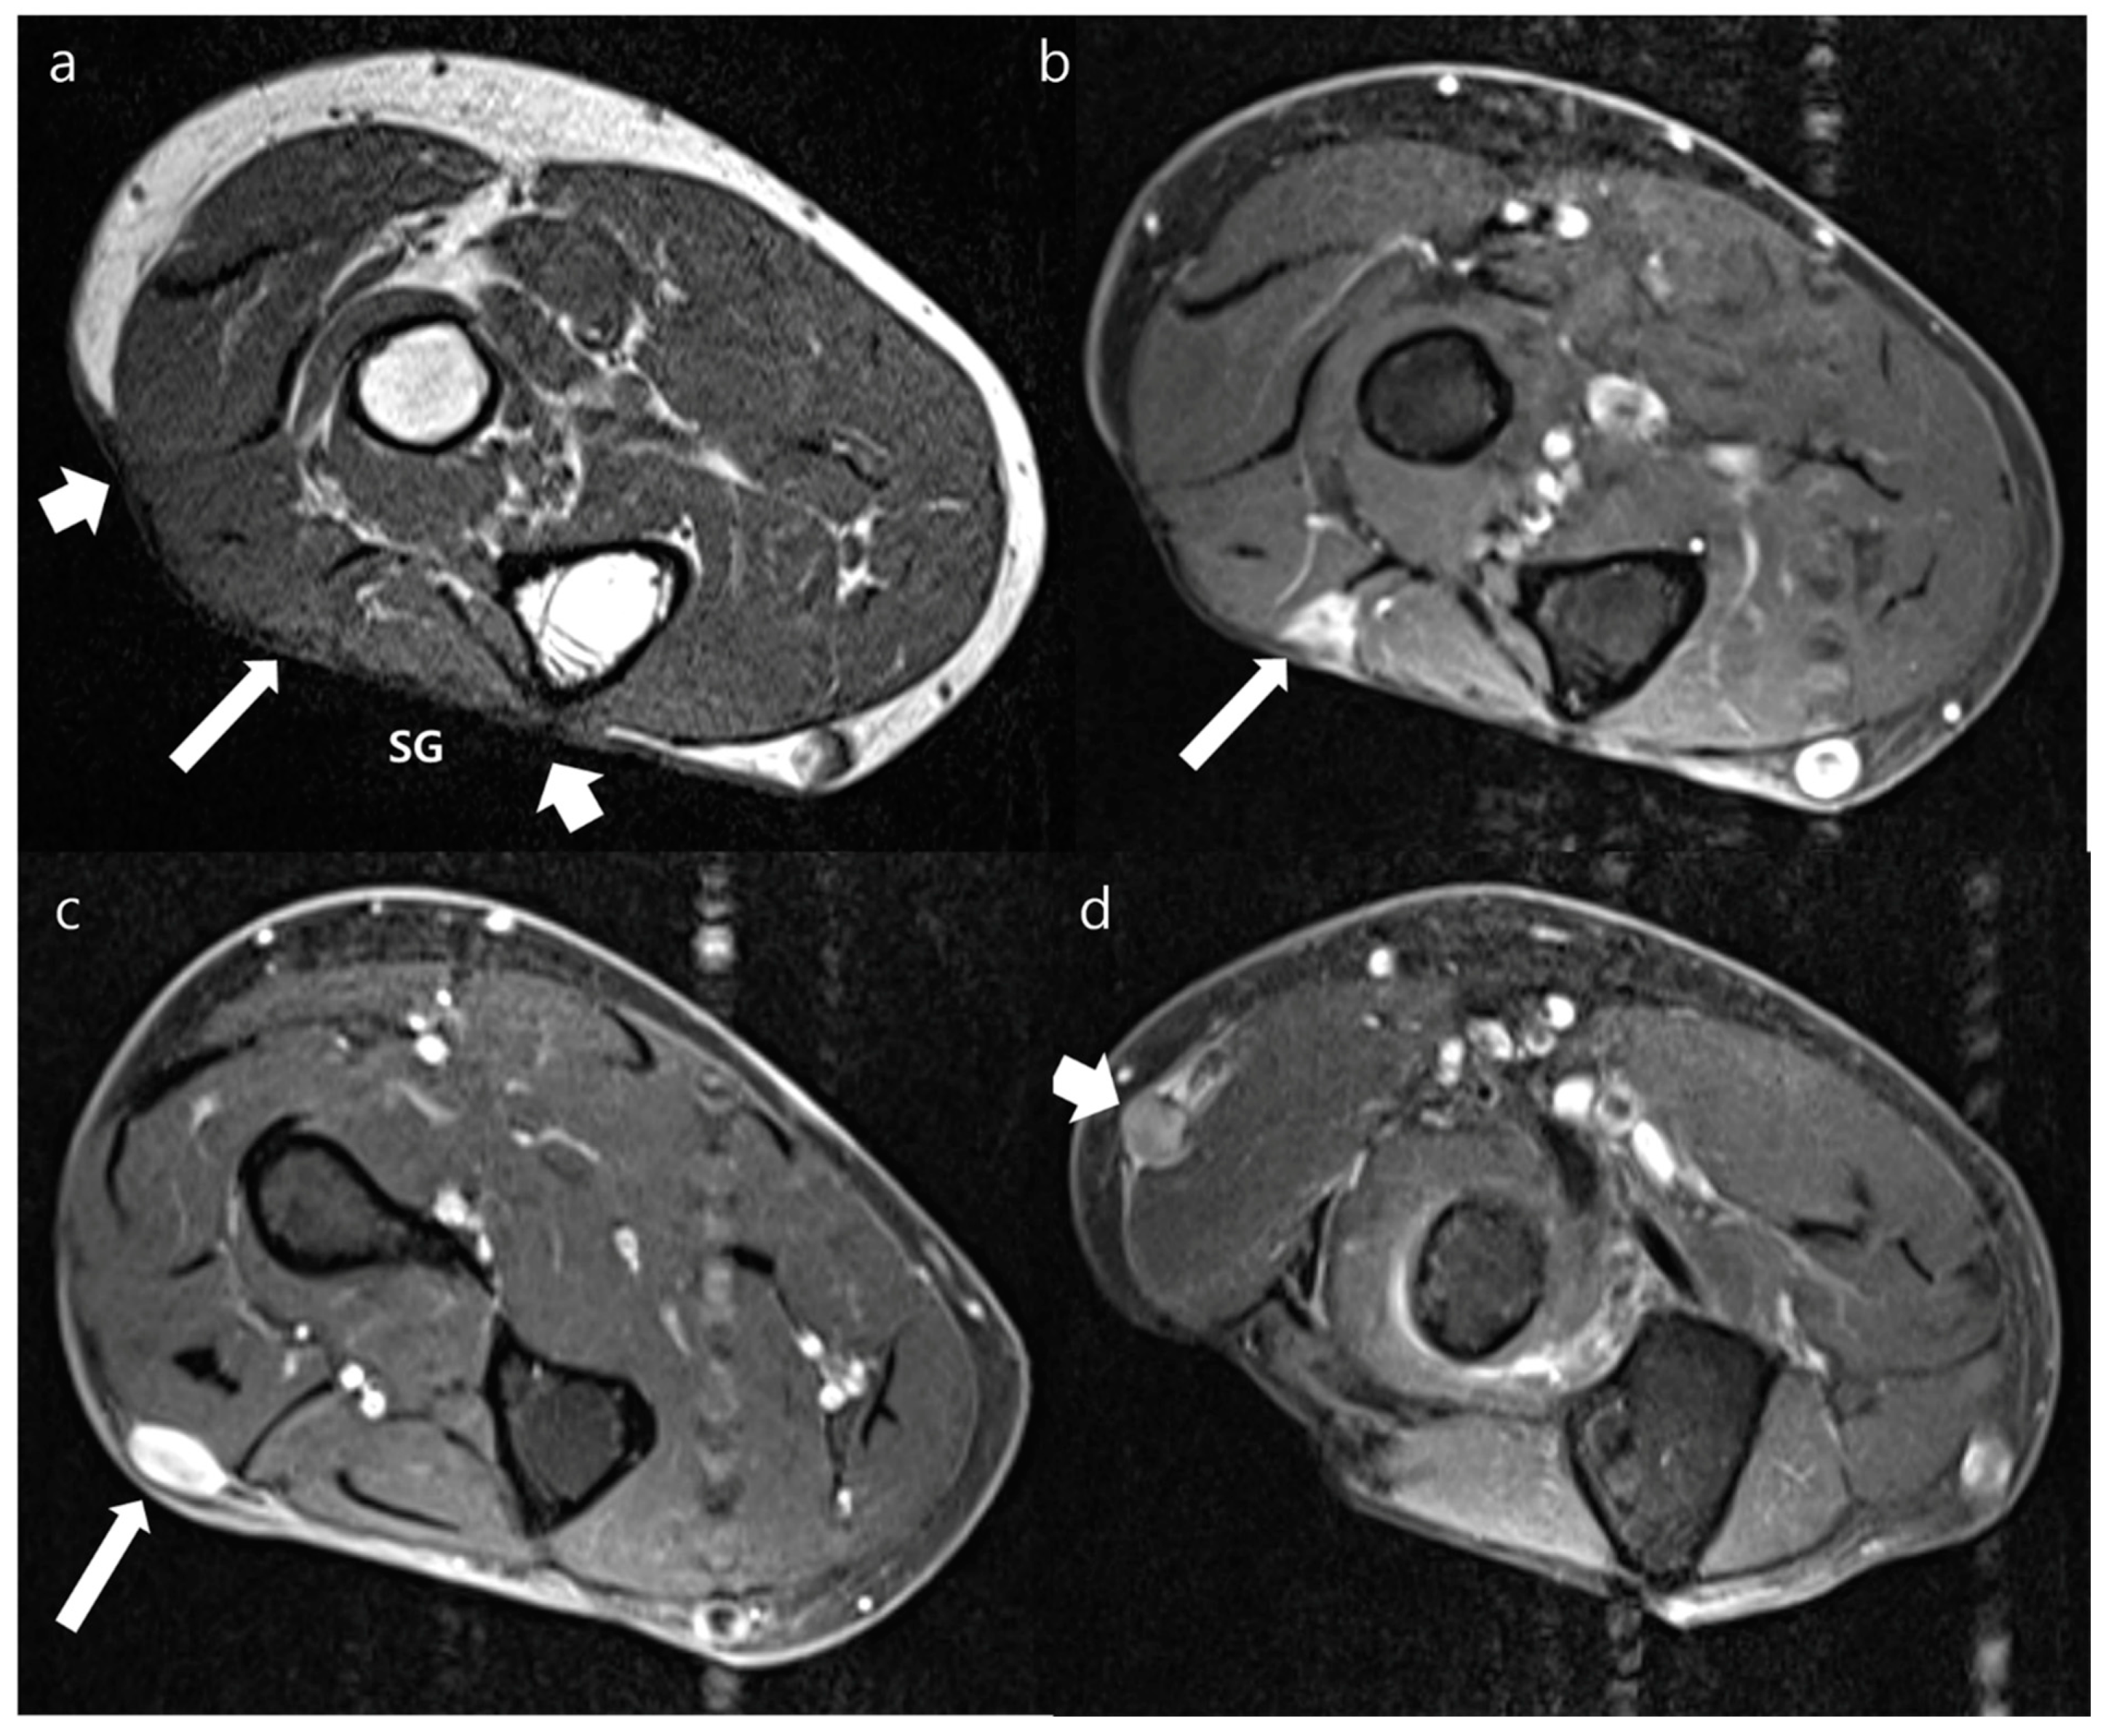

| Variables | Local Recurrences (n = 40) | Postoperative Changes (n = 36) | p Values | |

|---|---|---|---|---|

| Location on the transplanted soft tissue a | Peripheral margin | 25 | 22 | 0.907 |

| Deep margin | 11 | 12 | 0.583 | |

| Regional | 7 | 3 | 0.241 | |

| Border | Well-defined | 30 | 9 | <0.001 * |

| Ill-defined | 10 | 27 | ||

| Shape | Nodular | 39 | 20 | <0.001 * |

| Non-nodular | 1 | 16 | ||

| Size (cm) b | 2.6 ± 2.2 | 1.7 ± 1.0 | 0.020 * | |

| Sequences | Signal Intensity of MRI | Local Recurrences (n = 40) | Postoperative Changes (n = 36) | Hyperintensity vs. iso- or Hypointensity (p Value) |

| T1WI | Hyperintensity | 12 | 2 | 0.007 * |

| Isointensity | 26 | 31 | ||

| Hypointensity | 2 | 3 | ||

| T2WI | Hyperintensity | 34 | 15 | <0.001 * |

| Isointensity | 4 | 17 | ||

| Hypointensity | 2 | 4 | ||

| FS-T2WI | Hyperintensity | 38 | 27 | 0.020 * |

| Isointensity | 1 | 7 | ||

| Hypointensity | 1 | 2 | ||

| Contrast-enhanced FS-T1WI | Strong | 20 | 3 | <0.001 * |

| Moderate | 18 | 31 | ||

| Mild | 2 | 2 | ||

| DWI with high b-value | Hyperintensity | 37 | 30 | 0.294 |

| Isointensity | 1 | 4 | ||

| Hypointensity | 2 | 2 | ||

| ADC (μm2/s) a | 1297.0 ± 590.9 | 1634.6 ± 462.7 | 0.008 * | |

| Impeded water diffusion | Positive | 22 | 5 | <0.001 * |

| Negative | 18 | 31 | ||